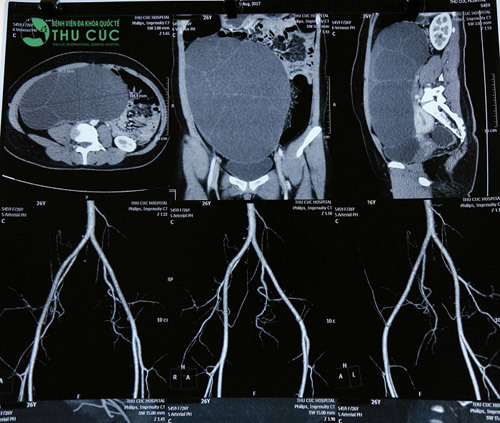

Khối u nang buồng trứng chiếm gần hết khoang bụng, có kích thước 25x20x10cm, đe dọa gây vỡ nếu không phẫu thuật sớm. |

Qua thăm khám và thực hiện các xét nghiệm cần thiết, các bác sĩ của Bệnh viện Thu Cúc cho hay khối u nang buồng trứng trong cơ thể chị T có kích thước 25x20x10cm, u chiếm phần lớn ổ bụng và đè đẩy vào các tạng. Nếu không phẫu thuật sớm, u đe dọa vỡ, gây nguy hiểm cho tính mạng.

Hình ảnh khối u trong phim chụp. |